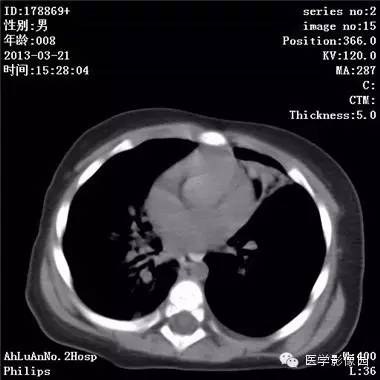

患儿男,8个月,呛咳,发热一周。实验室检查白细胞及中性粒细胞增高。

两肺肺纹理增多、增粗,右肺可见斑片状、片絮状模糊影,边界欠清;左肺上叶见楔形高密度影,内可见支气管征,尖端指向肺门;左肺下叶肺野透亮度增强;另见左肺主支气管内可见块状软组织密度影。

支气管异物(花生米)伴两肺炎症(追问病史,患儿奶奶层于一周前喂食患儿花生米,当时疑似“呛进去”,后来见好了也就没留意)。